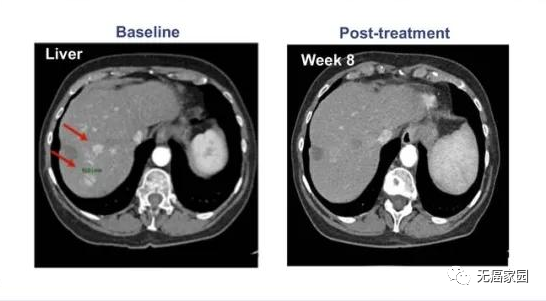

早在2020年国际肝病大会(ILC)上,一款基于T细胞的肝癌新型TCR-T疗法ADP-A2AFP引起了不小的轰动,也让肝癌的新疗法有了新的突破。

在纳入的患者中,有一名患者的癌细胞进程出现了完全缓解(CR)的表现,其余参与者的甲胎蛋白(AFP)也都出现了不同程度的下降,这意味着试验取得了进展,也说明该疗法针对晚期肝癌的治疗是有效果的。

参与的9例患者均接受过手术及常规放化疗,但出现失败或不耐受的现象。在接受最高剂量治疗的4例患者中,有1例患者获得完全缓解,CT扫描显示,患者体内所有病变都消失了,而且完全缓解后已持续半年以上无任何复发的状态!

其他患者(队列1、队列2)最佳反应是病情稳定。队列2中的1例患者在治疗1个月后原发病灶体积未缩小,但纵膈淋巴结转移灶体积明显缩小!

因此,靶向AFP(甲胎蛋白)的TCR-T疗法能够杀死表达AFP的肿瘤细胞,基于此项研究的积极结果,研究人员有望将最大剂量扩大至50亿个细胞治疗,我们期待这项研究更新的数据公开!